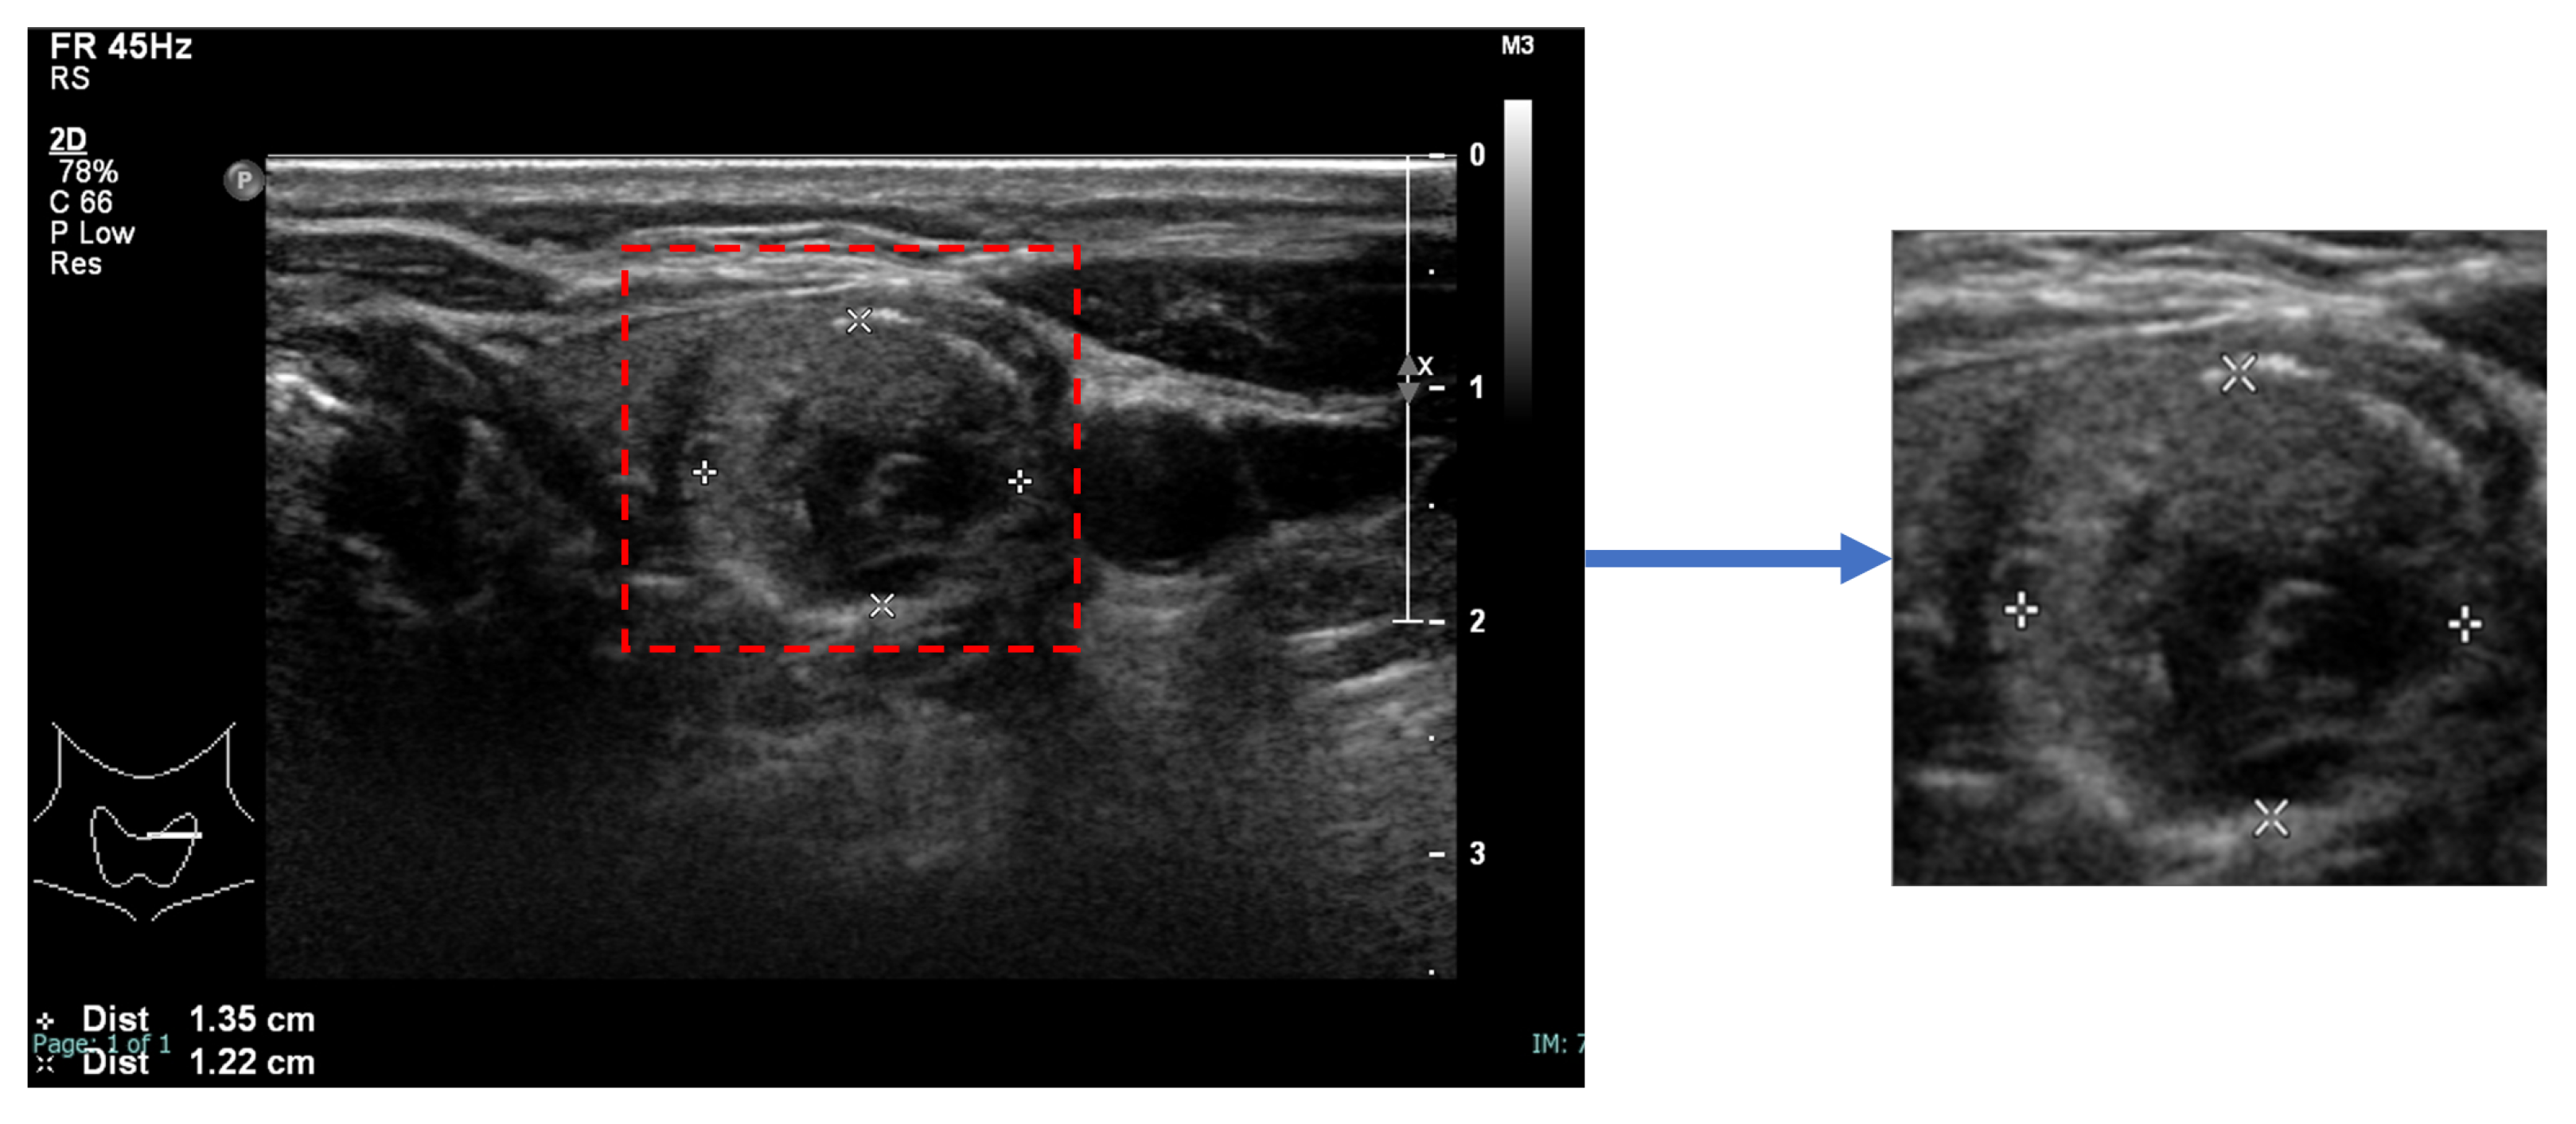

An image of each nodule, detected and segmented by StableSeg GANs [

24] in an ultrasound image, was cropped with a 5% margin and resized to 512 × 512, as shown in

Figure 2.

Figure 2.

Preparation of a nodule image. The nodule, segmented using StableSeg GANs, was cropped with a 5% margin and then resized to 512 × 512 pixels.

Figure 2.

Preparation of a nodule image. The nodule, segmented using StableSeg GANs, was cropped with a 5% margin and then resized to 512 × 512 pixels.